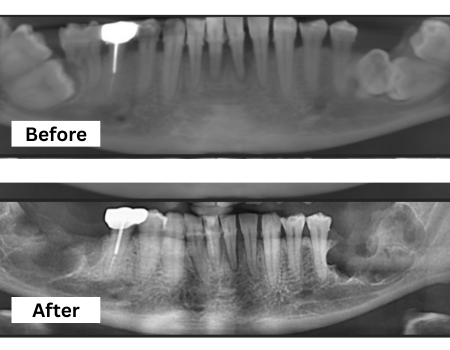

Wisdom Tooth Surgery

Safe, precise removal of impacted or problematic wisdom teeth to prevent pain, infection, and misalignment of surrounding teeth.